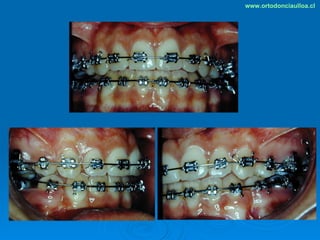

Este documento presenta dos casos clínicos de pacientes que recibieron tratamiento de ortodoncia. El primer caso fue de una paciente femenina de 14 años con apiñamiento dental y mordida cruzada que fue tratada mediante extracción de premolares y alineamiento dental. El segundo caso fue de un paciente masculino de 14 años con clase II esqueletal y desarmonía dentomaxilar que fue tratado con extracción de premolares y corrección de mordida. Ambos casos mostraron mejoría después de 3 años de tratamiento.